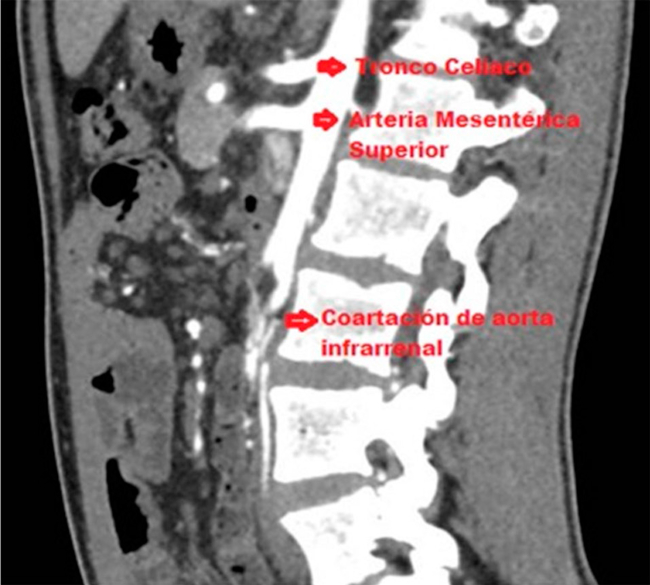

Se presenta el caso de un varón de 21 años que consulta por claudicación intermitente. Tiene como antecedentes coartación aórtica torácica tratada en el año 2013 con un stent y una angioplastia con balón de la arteria ilíaca derecha secundaria a una estenosis. En el examen físico, se evidenció facies con un fenotipo peculiar, dimorfismo de pabellones auriculares, párpados y paladar, asociado con supinación de ambos codos (Figura 1). La evaluación genética fue compatible con un síndrome de Noonan. Los pulsos periféricos y resultados de laboratorio fueron normales. Se realizó una angiotomografía, en la que se evidenció una estenosis suboclusiva de la aorta infrarrenal con recanalización en las arterias ilíacas internas a través de las arterias iliolumbares y la arteria mesentérica inferior (Figura 2). Además, se observó hipotrofia de ambas arterias ilíacas primitivas en su origen, pero con flujo adecuado en la zona distal. La angiografía con sustracción digital mostró una válvula aórtica competente y una raíz aórtica no dilatada. El stent se visualizó permeable y sin parámetros de reestenosis, localizado distalmente al origen de la arteria subclavia. Además, se confirmó una coartación aórtica abdominal infrarrenal asociada a una lesión significativa y larga en la arteria ilíaca primitiva derecha y una oclusión completa de la arteria ilíaca primitiva izquierda. Se completó evaluación con ecocardiograma y ergometría que fueron normales. Se realizó un bypass aortoilíaco de forma electiva con prótesis de dacron. Luego de 4 d de internación, el paciente fue dado de alta sin ninguna complicación. En el posoperatorio inmediato, se evidenció una correcta perfusión de las extremidades inferiores con un alivio completo de los síntomas. Específicamente, la hipoplasia aórtica infrarrenal carece de una definición clara. Sin embargo, clásicamente se presenta como un segmento de arteria aorta con un diámetro inferior a 12 mm. Existen cuatro tipos de coartación aórtica, tipo I: coartación suprarrenal y estenosis de arteria renal; tipo II: coartación infrarrenal y estenosis de arteria renal; tipo III: coartación suprarrenal y arterias renales normales; tipo IV: coartación infrarrenal y arteria renal normal. Por ende, nuestro paciente pertenece al grupo III/IV. Su tratamiento es discutible y, con el advenimiento de técnicas endovasculares, se plantea su utilidad en esta patología. No obstante, como en general son estenosis largas prevalece la cirugía convencional sobre los métodos endovasculares. Las escasas series de casos son en su mayoría de cirugía convencional. No existen trabajos que comparen una técnica con la otra, por lo que no es posible establecer diferencias en el éxito técnico y los resultados en el tiempo entre ambos métodos. En nuestro paciente, el tratamiento endovascular resultó satisfactorio para la estenosis de la aorta torácica con un período de permeabilidad de más de quince años. Dada la longitud de la estenosis y la evidencia bibliográfica se decidió el abordaje quirúrgico convencional. El paciente, luego de un año de la cirugía, tiene una vida sin limitación en sus actividades, aunque aún estaría pendiente su valoración en el tiempo.